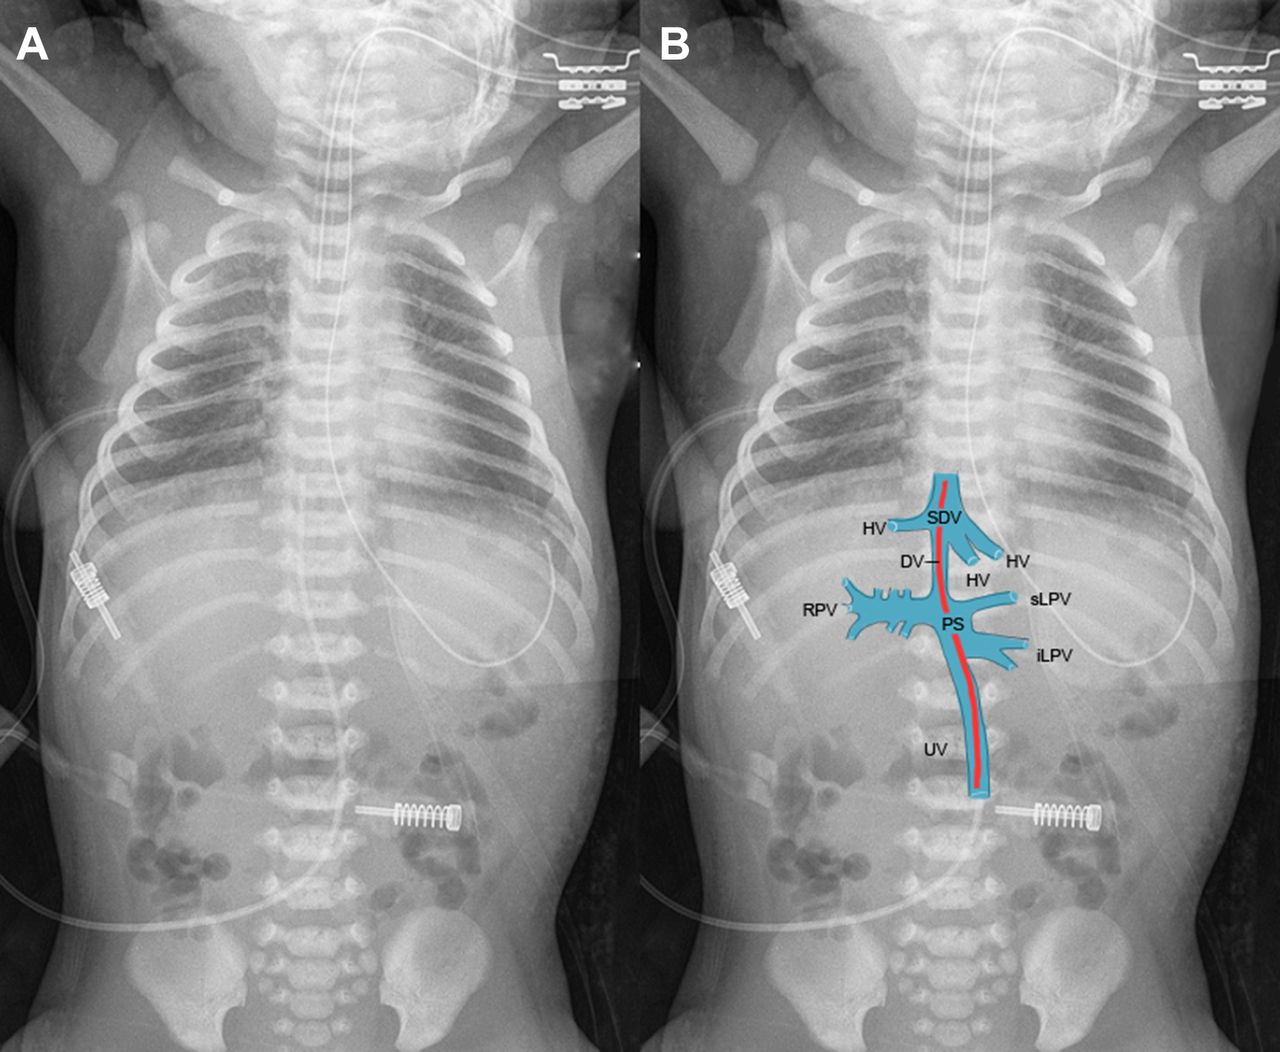

Experiencing a hernia belly button? Discover the symptoms, causes, and effective treatment options for an umbilical hernia. Learn how to identify this common abdominal bulge, understand the risks of complications, and explore when surgical repair is necessary to relieve discomfort and restore your health. Get expert insights on managing your recovery effectively and safely.